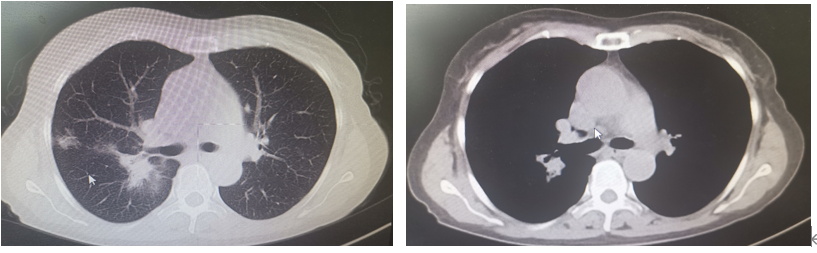

纵隔内右头臂静脉后、腔静脉旁及右上肺门多发结节,PET-CT显像可见放射性浓聚,考虑淋巴结转移。

-

骶骨,双侧髂骨,PET-CT显像可见放射性浓聚,考虑转移。